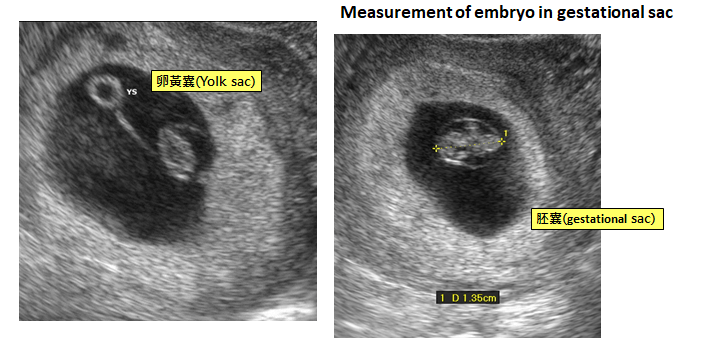

- 陰道超音波在懷孕5至5週可見胚囊(gestational sac),5至6週則可見到卵黃囊(yolk sac)直到第10周,5.5至6週可檢測到具有心臟活動。(圖二)

圖二 胚囊(gestational sac)與卵黃囊(yolk sac) 圖片來源:UpToDate—Clinical manifestations and diagnosis of early pregnancy